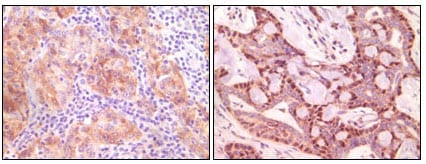

分类: 科研抗体货号: 20085别名: MGC10442应用: IHC反应种属: Human

分类: 科研抗体货号: 20090别名: MGC10442应用: IHC反应种属: Human